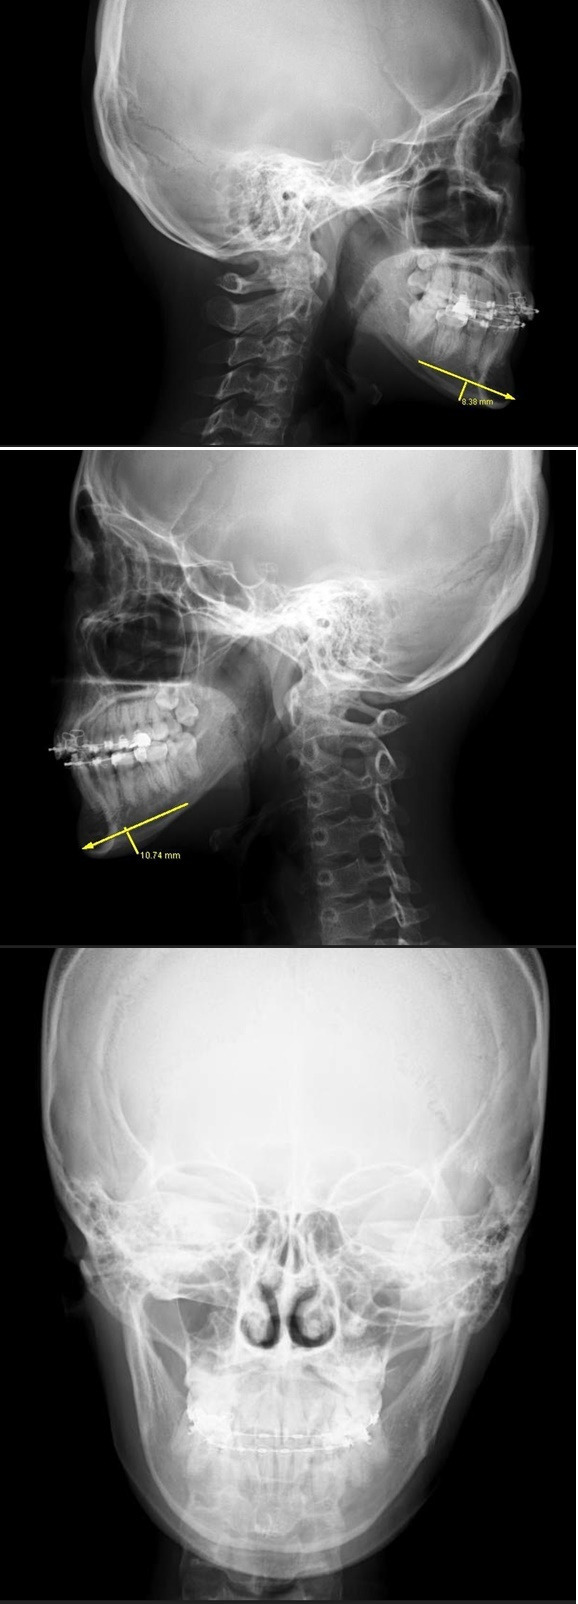

レントゲン正面写真では、

左右ともに下顎骨の中央部あたりに丸みがあり、

左側のほうが右に比べ張り出ています。

左側を少し大きめに切ったほうが良さそうです。

ただし顎は決して長くはないので、

中央部は5mm幅で、左は10mm強、

右は9mm弱切ることとしました。